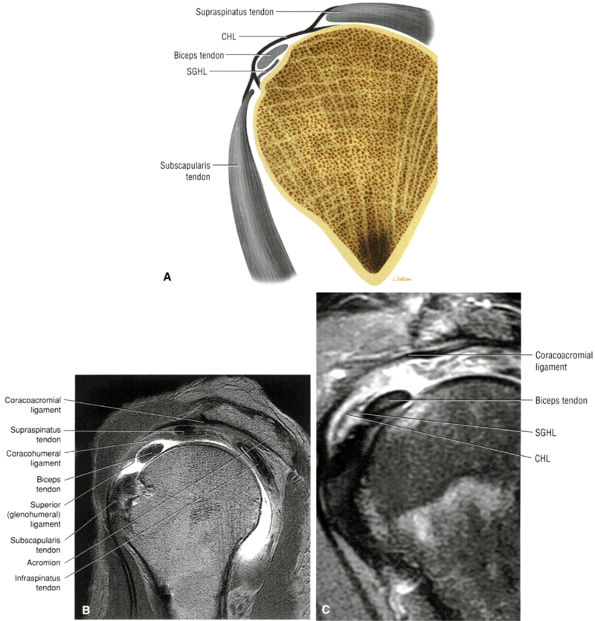

FIGURE 8.92 ● Coronal PD-weighted images showing (A) the lateral band of the coracohumeral ligament inserting on the greater tuberosity and anterior border of the supraspinatus and (B) the medial band of the coracohumeral ligament inserting on the lesser tuberosity, the superior fibers of the subscapularis, and the transverse ligament.

FIGURE 8.93 ● The coracohumeral ligament (CHL) inserts on either side of the bicipital groove rotator interval. The CHL and the superior glenohumeral ligament help stabilize the biceps tendon by forming a biceps pulley.